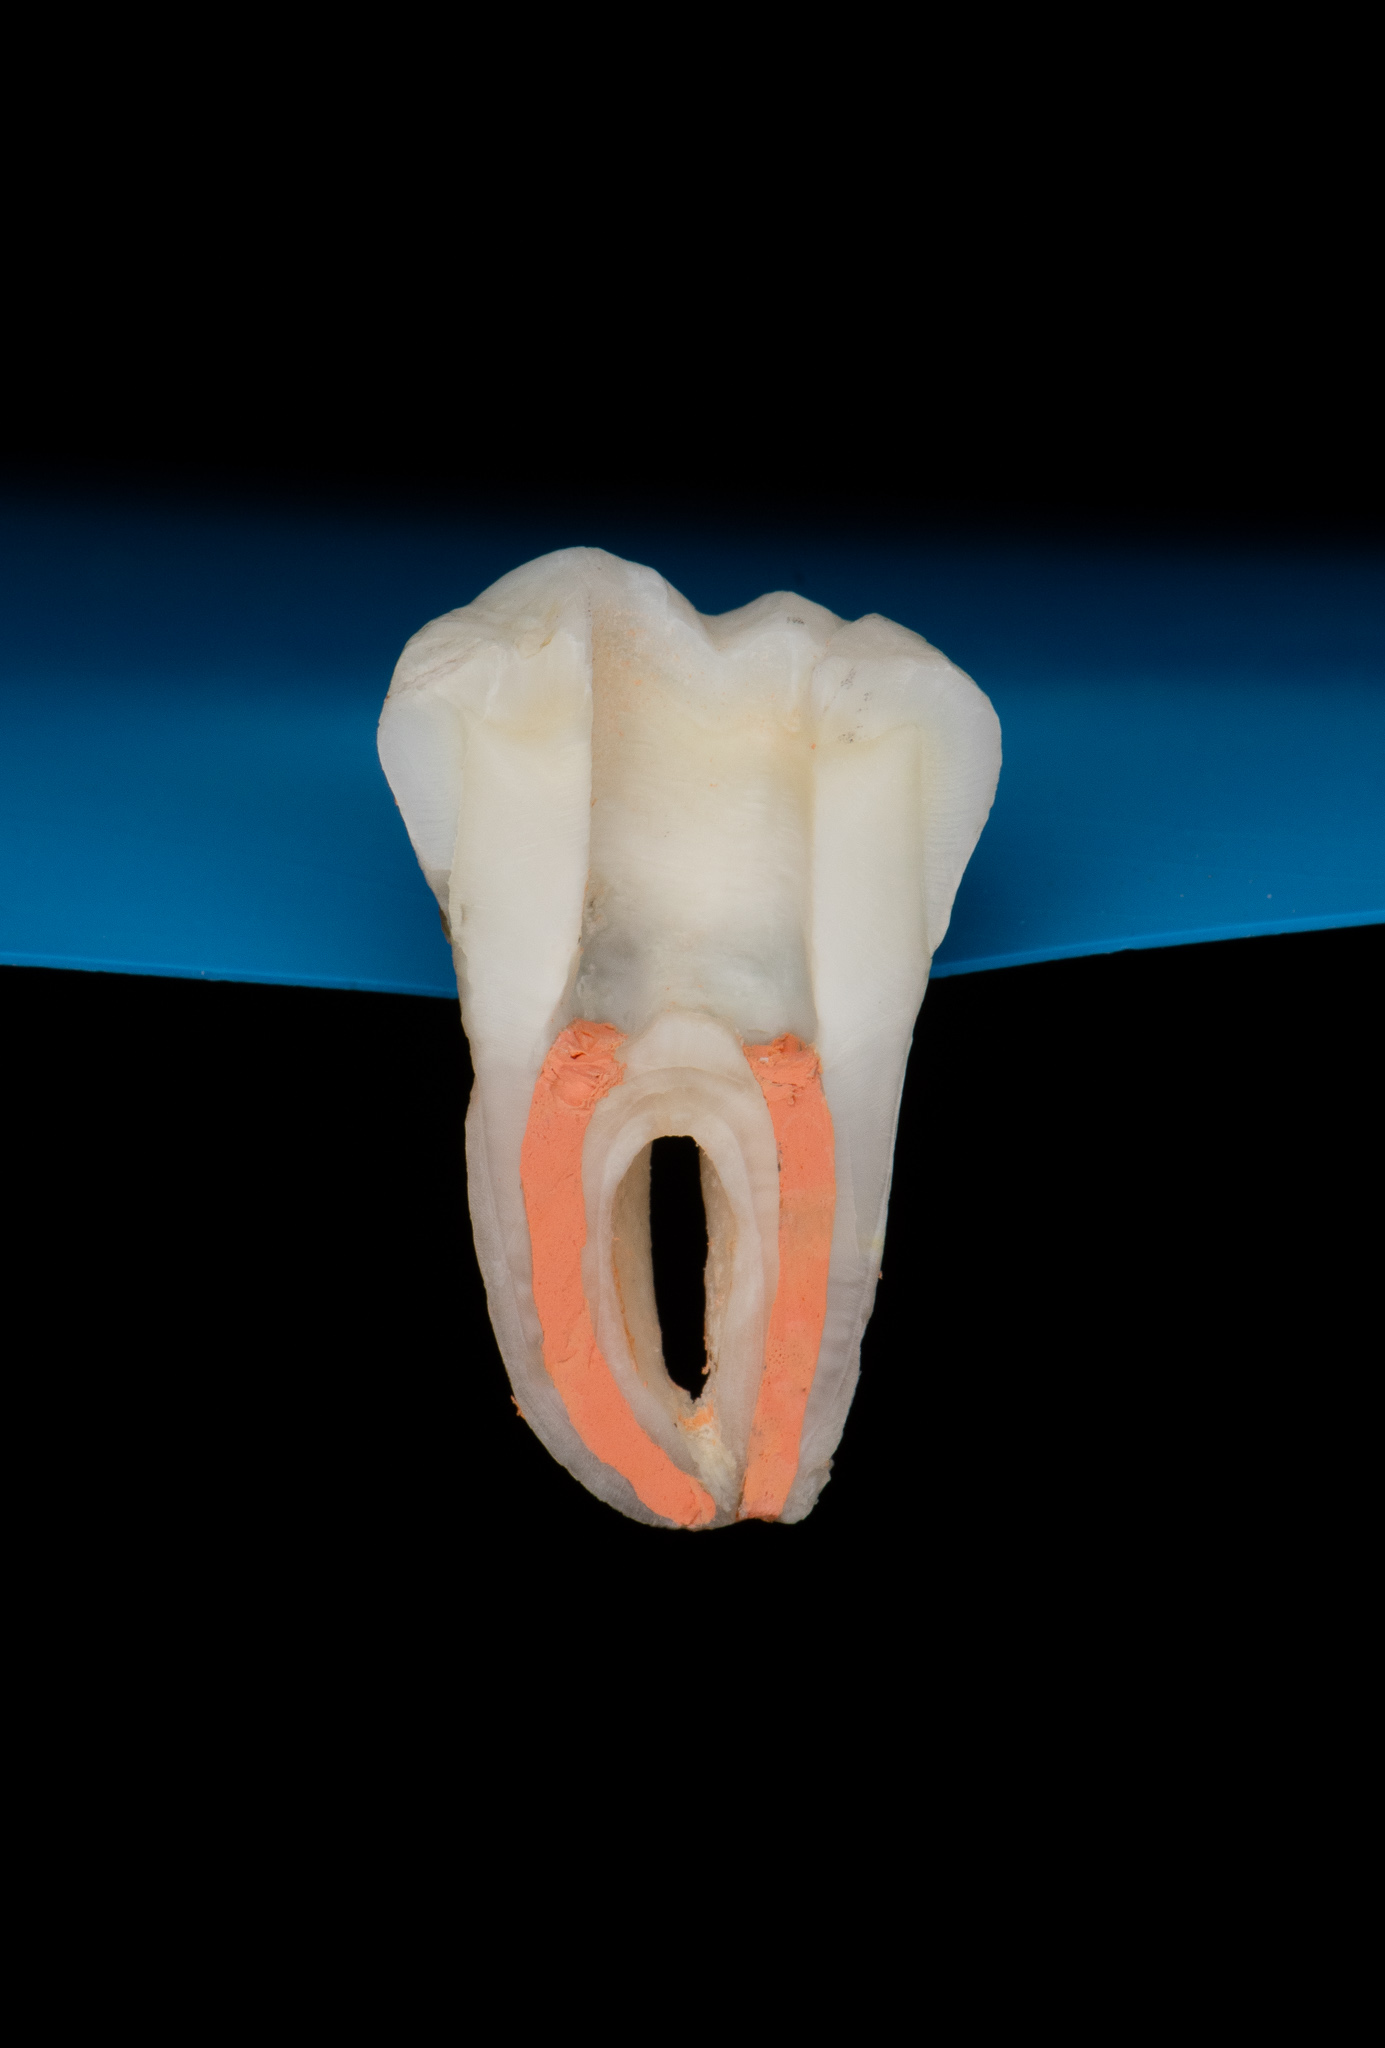

Endodoncja czyli leczenie kanałowe pozwala, na wiele lat, utrzymać w zdrowiu zęby martwe, które w przeciwnym razie wymagałby usunięcia. W naszym gabinecie prowadzimy leczenie kanałowe pierwotne jak również powtórne (ReEndo) z wykorzystaniem nowoczesnych technik i narzędzi takich jak mikroskop zabiegowy, rotacyjne systemy udrażniania kanałów czy wypełnienie płyną falą gutaperki.

Pacjent zgłosił się do gabinetu w celu zaopatrzenia złamanego zęba (kła) w koronę protetyczną. W badaniu radiologicznym widoczna jest resorpcja materiału wypełniającego kanał po dawnym leczeniu endodontycznym oraz tworząca się zmiana zapalna w okolicy wierzchołka korzenia; z uwagi na konieczność wykorzystania zęba jako filar protetyczny przeprowadzono powtórne leczenie kanałowe (ReEndo) z wykorzystaniem nowoczesnych narzędzi rotacyjnych oraz mikroskopu zabiegowego. Kanał wypełniono szczelnie techniką obturacji płynną falą gutaperki (wypełnienie na ciepło).